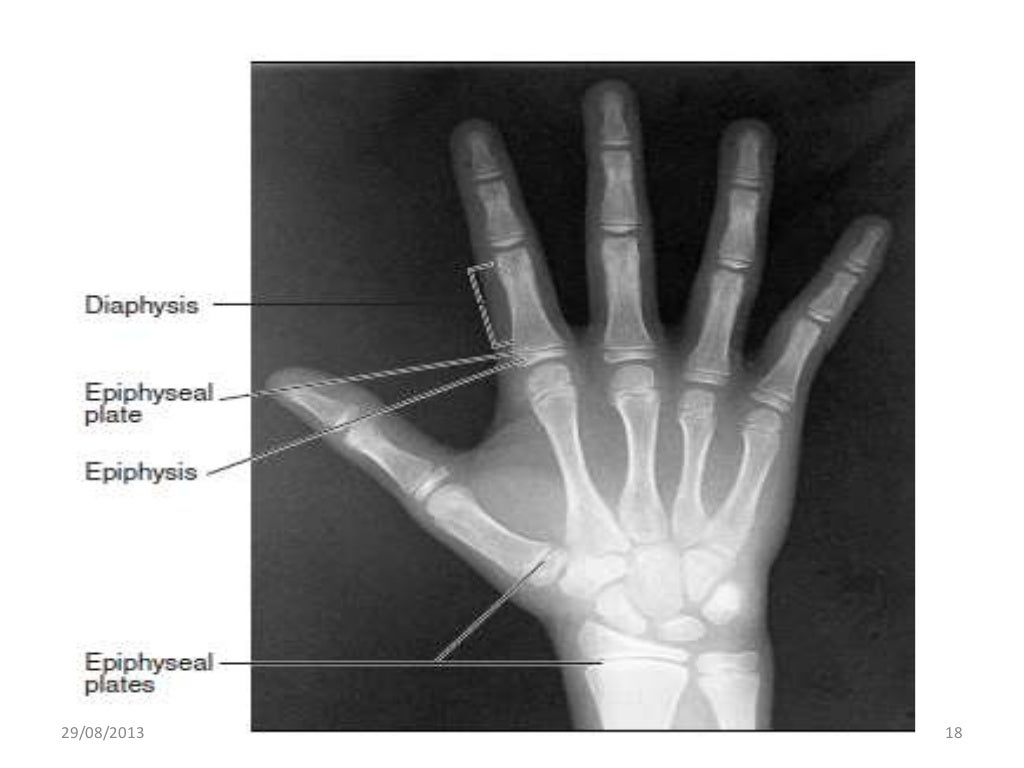

wrist anatomy pics

wrist anatomy pics Hand Wrist Radiograph In Orthodontics The hand and wrist radiograph help in estimating the skeletal age of bone for determining the physical maturation status of the child. The hand wrist radiograph is considered to be the most standardized method of skeletal assessment. 7 clinical questions focused on orthopantomograms, lateral cephalograms,. In the present review we will discuss about the various methods of. The pubertal growth. Hand Wrist Radiograph In Orthodontics.

From anatomybody99.storage.googleapis.com